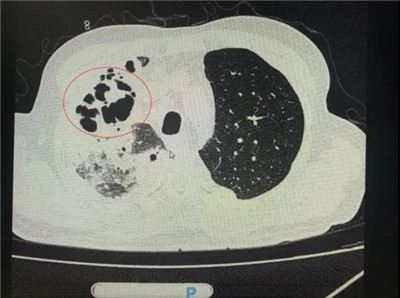

番禺院区呼吸内科何梦璋主任接诊后,对钟叔进行详细检查。此时,钟叔的病情已经十分危急,由于不能自主呼吸,他带上了无创呼吸机辅助呼吸治疗。看到钟叔胸片时,医护人员头皮也一阵发麻,胸部CT可见双肺多发的炎症浸润、双肺多发空洞。通俗来说,钟叔的肺部已经被病原体蚕食,啃出无数个大小各异的洞!可怕的是,这种病变对肺功能的破坏是永久性、不可恢复的。根据钟叔病史以及胸部CT结果,最终诊断为“吸入性肺脓肿”。

钟叔的肺部被病原体蚕食,啃出无数个大小各异的洞。